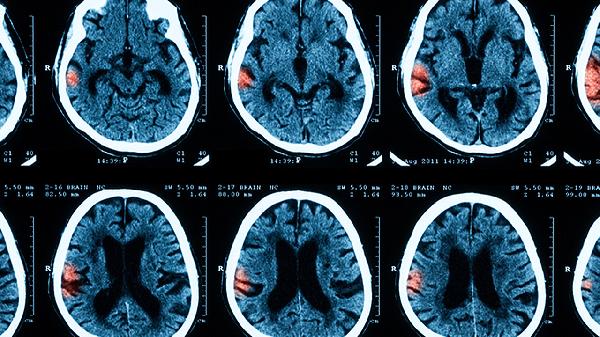

部分患者可能因病情严重或治疗不及时,遗留神经系统后遗症。重症败血病脑膜炎可能出现脑水肿、脑疝等严重并发症,甚至危及生命。免疫功能低下、婴幼儿、老年人等特殊人群,治疗难度可能增加。这类患者需更长时间的治疗和康复,部分可能遗留听力下降、认知功能障碍等问题。